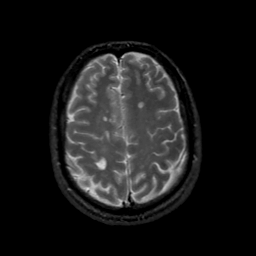

MR Study #18, July 21, 1991 -- Slice #38

[Home][Help][Clinical][Tour 1][Tour 2] Slice 38